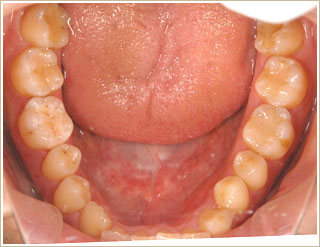

一切金属を使わずに修復。

足に出来る湿疹で悩み、知人の紹介で受診される。長期間皮膚科にて治療を受けるが、改善されず。口の中の金属を外し、ノンメンタル治療を行う。

▼治療前

▼治療後